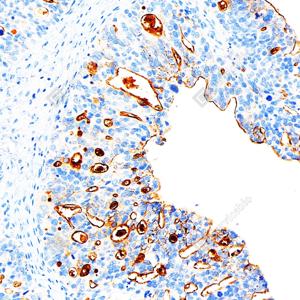

IHC检测CA125/MUC16蛋白(货号 GB15017). 样品: 人子宫内膜癌, 4%多聚甲醛 (货号G1101) 固定12-24小时. 抗原修复: 柠檬酸抗原修复液(干粉, pH 6.0) (G1201), 高压锅均匀喷气计时2分钟. —抗: 1: 500稀释, 4℃ 孵育过夜. 二抗: S-vision免疫组化多聚二抗(山羊抗小鼠), 即用型(货号G1301), 室温孵育20分钟. |